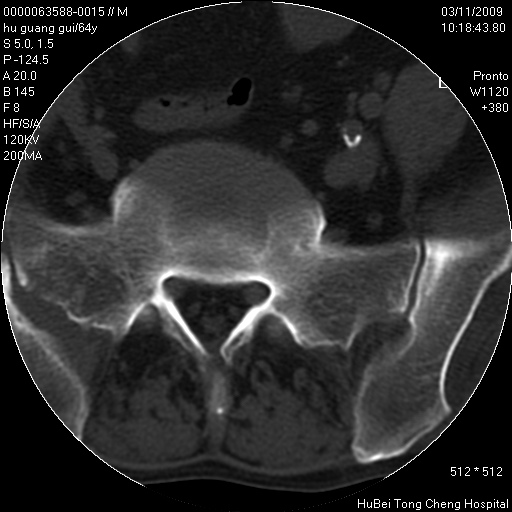

患者 男,64岁。腰痛十余天。(临床未提供其他病史)

临床诊断:腰痛原因待查(腰椎间盘突出症?)。

腰椎间盘ct轴位平扫(层厚5mm,层距4mm),图像如下:

腰椎退行性变,腰4—5椎间盘膨出。

右侧骶骨侧块骨侵蚀,骶髂关节骨性关节面破坏,并见软组织肿块,考虑骨转移瘤可能,进一步检查。

1.腰椎退行性变,腰4—5椎间盘膨出。

2.右侧骶骨侧块骨侵蚀,骶髂关节骨性关节面破坏,并见软组织肿块,考虑:脊索瘤,骨转移瘤可能,进一步检查。

1)腰椎退行性变,l4—5椎间盘膨出。2)骶骨右侧块骨转移瘤可能,3)水平骶椎。建议作一步检查。